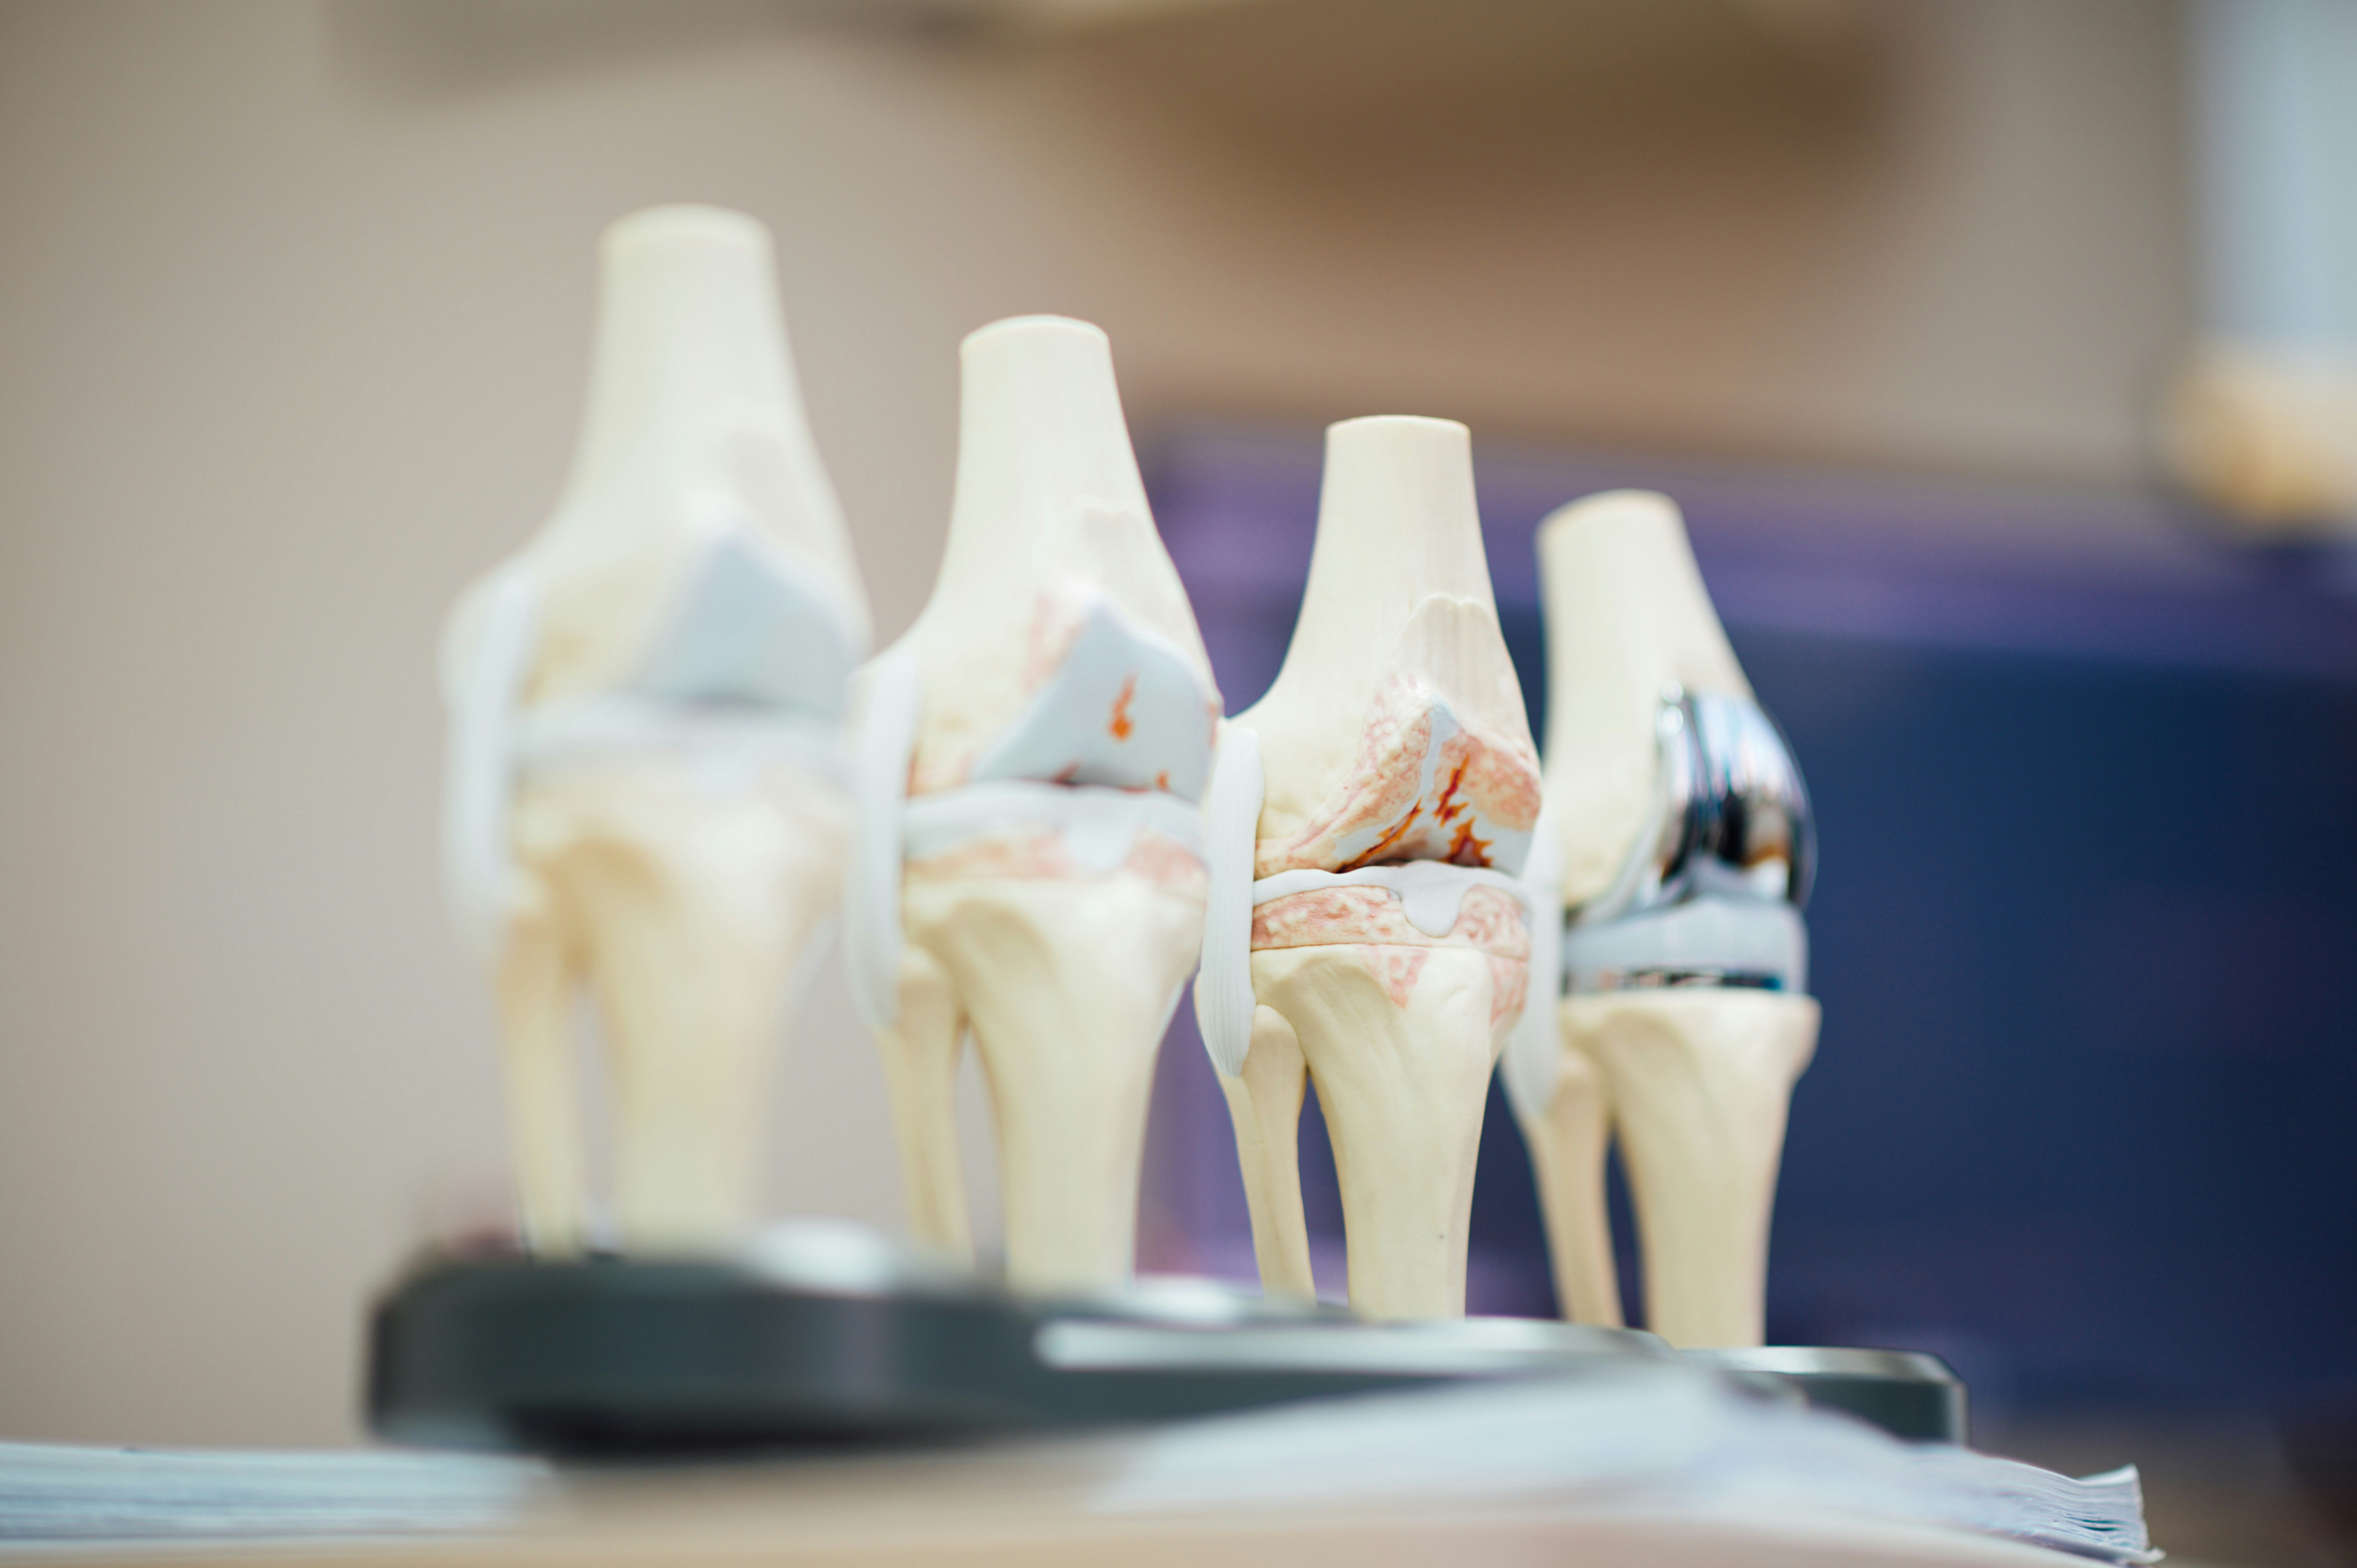

가장 흔한 원인은 무릎 관절을 보호하고 있는 **연골의 마모**입니다. 오랜 시간 관절을 사용하면서 연골이 얇아지고 뼈와 뼈가 직접 부딪히게 되는데, 이 과정에서 염증과 극심한 통증이 발생합니다. 주로 하중을 많이 받는 무릎 안쪽에 나타나며, 오랫동안 쪼그려 앉거나 무리한 동작을 반복할 때 퇴행 단계에 기여합니다.

무릎 관절을 부드럽게 움직이게 해주는 윤활유 역할을 하는 '활막'에 염증이 생기는 질환입니다. 무릎이 붓고 열이 나며, 움직일 때 뻐근한 통증이 느껴집니다. 급성으로 나타나기도 하지만, 퇴행성 관절염의 초기 증상으로 나타나기도 하므로 주의 깊은 관찰이 필요합니다.